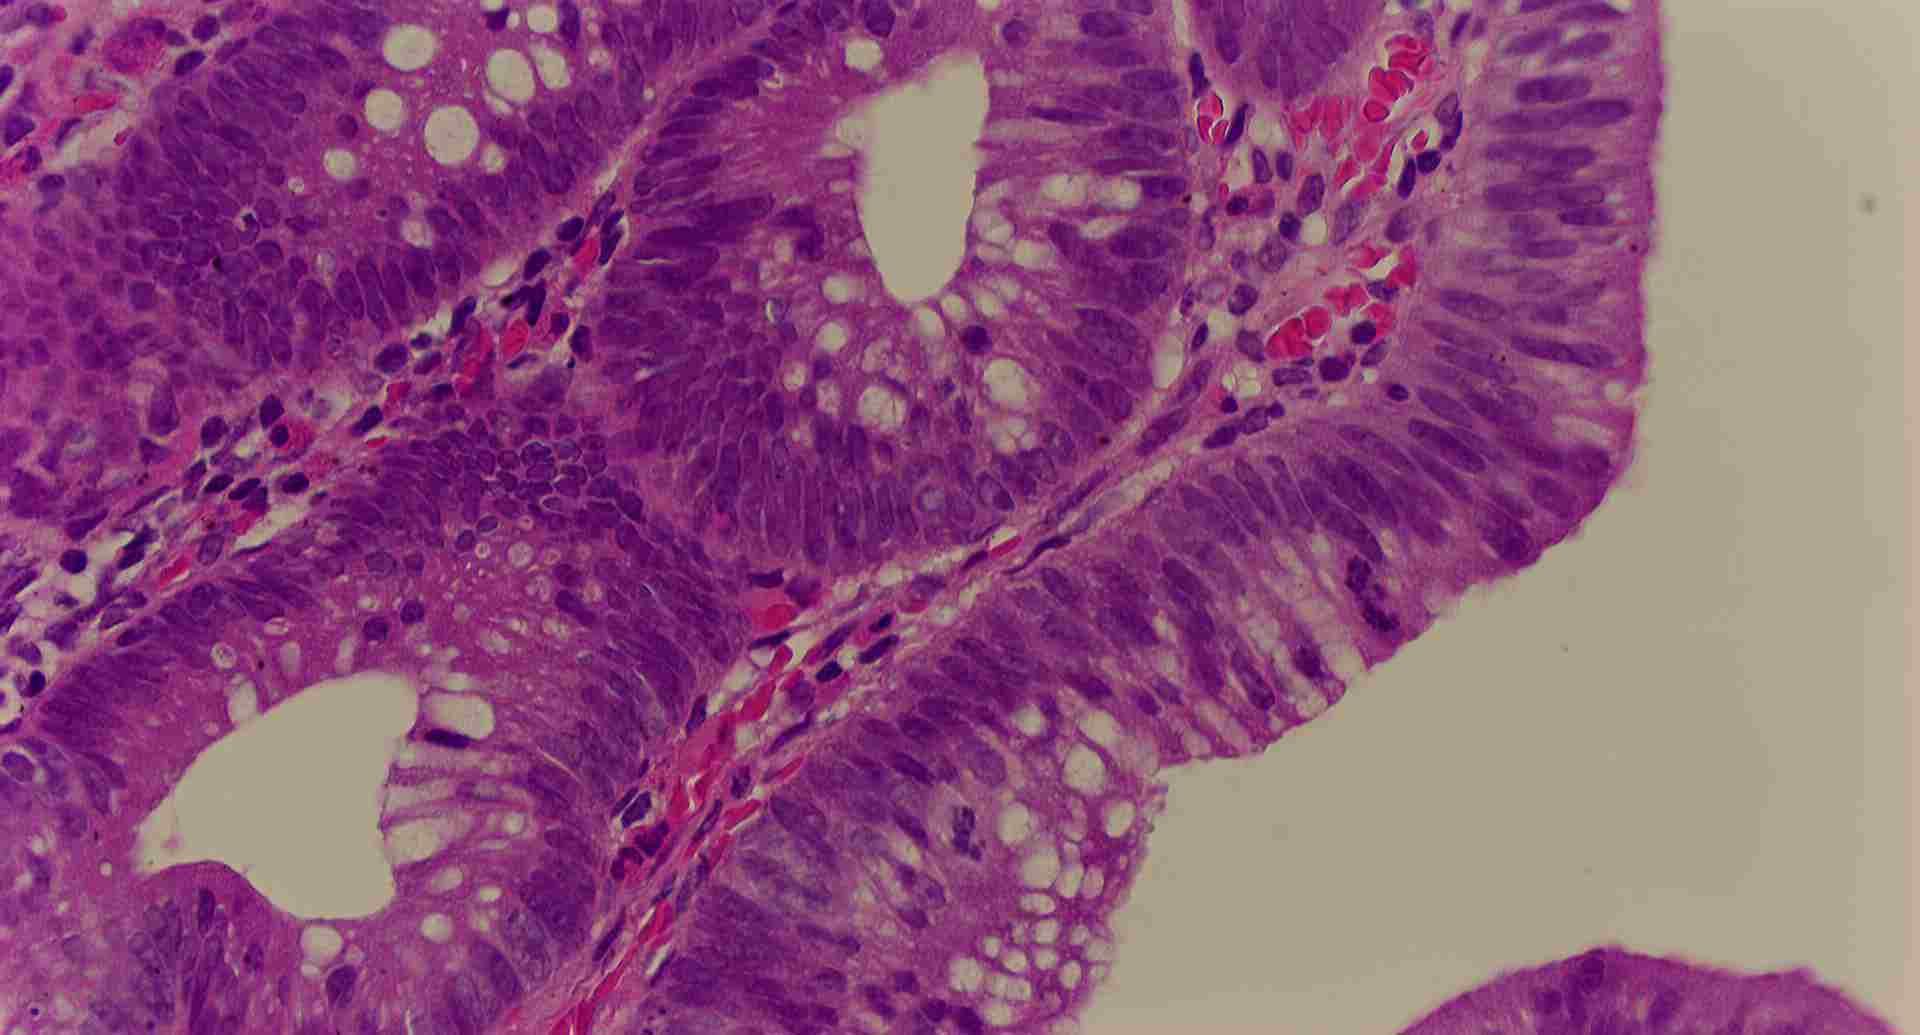

標本12

標本12の説明